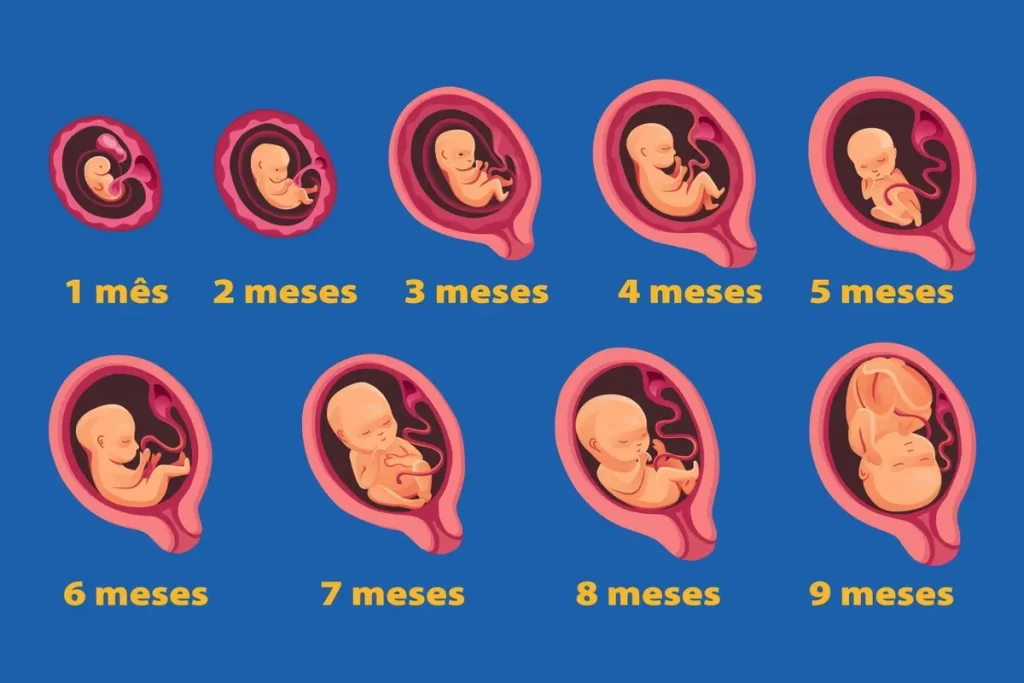

Como é o desenvolvimento fetal mês a mês?

O desenvolvimento mês a mês revela detalhes ainda mais específicos sobre a evolução do bebê. Essa análise permite compreender os marcos de cada fase, como o surgimento de sentidos, mudanças corporais e evolução do peso.

Destaques de cada mês

No terceiro mês, os órgãos vitais já estão formados, enquanto no quinto, o bebê começa a ouvir sons externos. No sétimo, os pulmões estão quase prontos, e no nono mês o organismo está preparado para a vida fora do útero.

Evolução de peso e tamanho aproximado

O bebê cresce de alguns gramas nas primeiras semanas para cerca de três quilos no final da gestação. Esse ganho reflete não apenas o crescimento físico, mas também o desenvolvimento funcional dos sistemas.